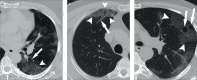

Results: A total of 250 patients were finally diagnosed with COVID-19. Clinical and laboratory findings included myalgia or fatigue (76%), fever (64.8%), dry cough (60.8%), elevated levels of C-reactive protein (86.4%), procalcitonin (62%), and D-dimer (58.2%), increased neutrophil-lymphocyte ratio (NLR) (54.8%), and lymphopenia (34%). Sensitivity, specificity, positive predictive value (PPV) and negative predictive value (NPV) of the initial CT scan were 90.4% (95% IC, 86%-93%), 64.2% (95% IC, 50%-76%), 91.8% (95% IC, 88%-94%), and 60% (95% IC, 49%-69%), respectively. The percentage of patients diagnosed on the initial rRT-PCR test was 51.6% (n=129). Most frequent CT characteristics of COVID-19 in the subgroup of rRT-PCR-positive patients were multiple lesion (97.4%, n=220), followed by bilateral involvement (88.5%, n=200), peripheral distribution (74.3%, n=168), ground-glass opacity (GGO) (69.2%, n=157), subpleural curvilinear opacity (41.6%, n=104), and mixed GGOs (27.6%, n=67).

Conclusion: rRT-PCR may produce initial false negative results. For this reason, typical CT findings for COVID-19 should be known especially by radiologists. We suggest that patients with typical CT findings but negative rRT-PCR results should be isolated, and rRT-PCR should be repeated to avoid misdiagnosis.